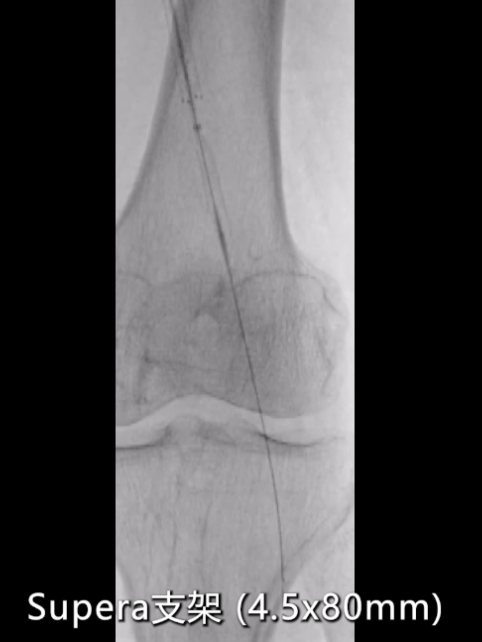

支架植入:由于该病变部位已临近P2,选择4.5×80mm Supera编织型支架,定位于P1-P2段交界处,完全覆盖病变段。

即时造影:支架贴壁良好,病变段完全覆盖,膝下腓动脉及胫后动脉显影明显改善,胫后动脉血流可至足趾;